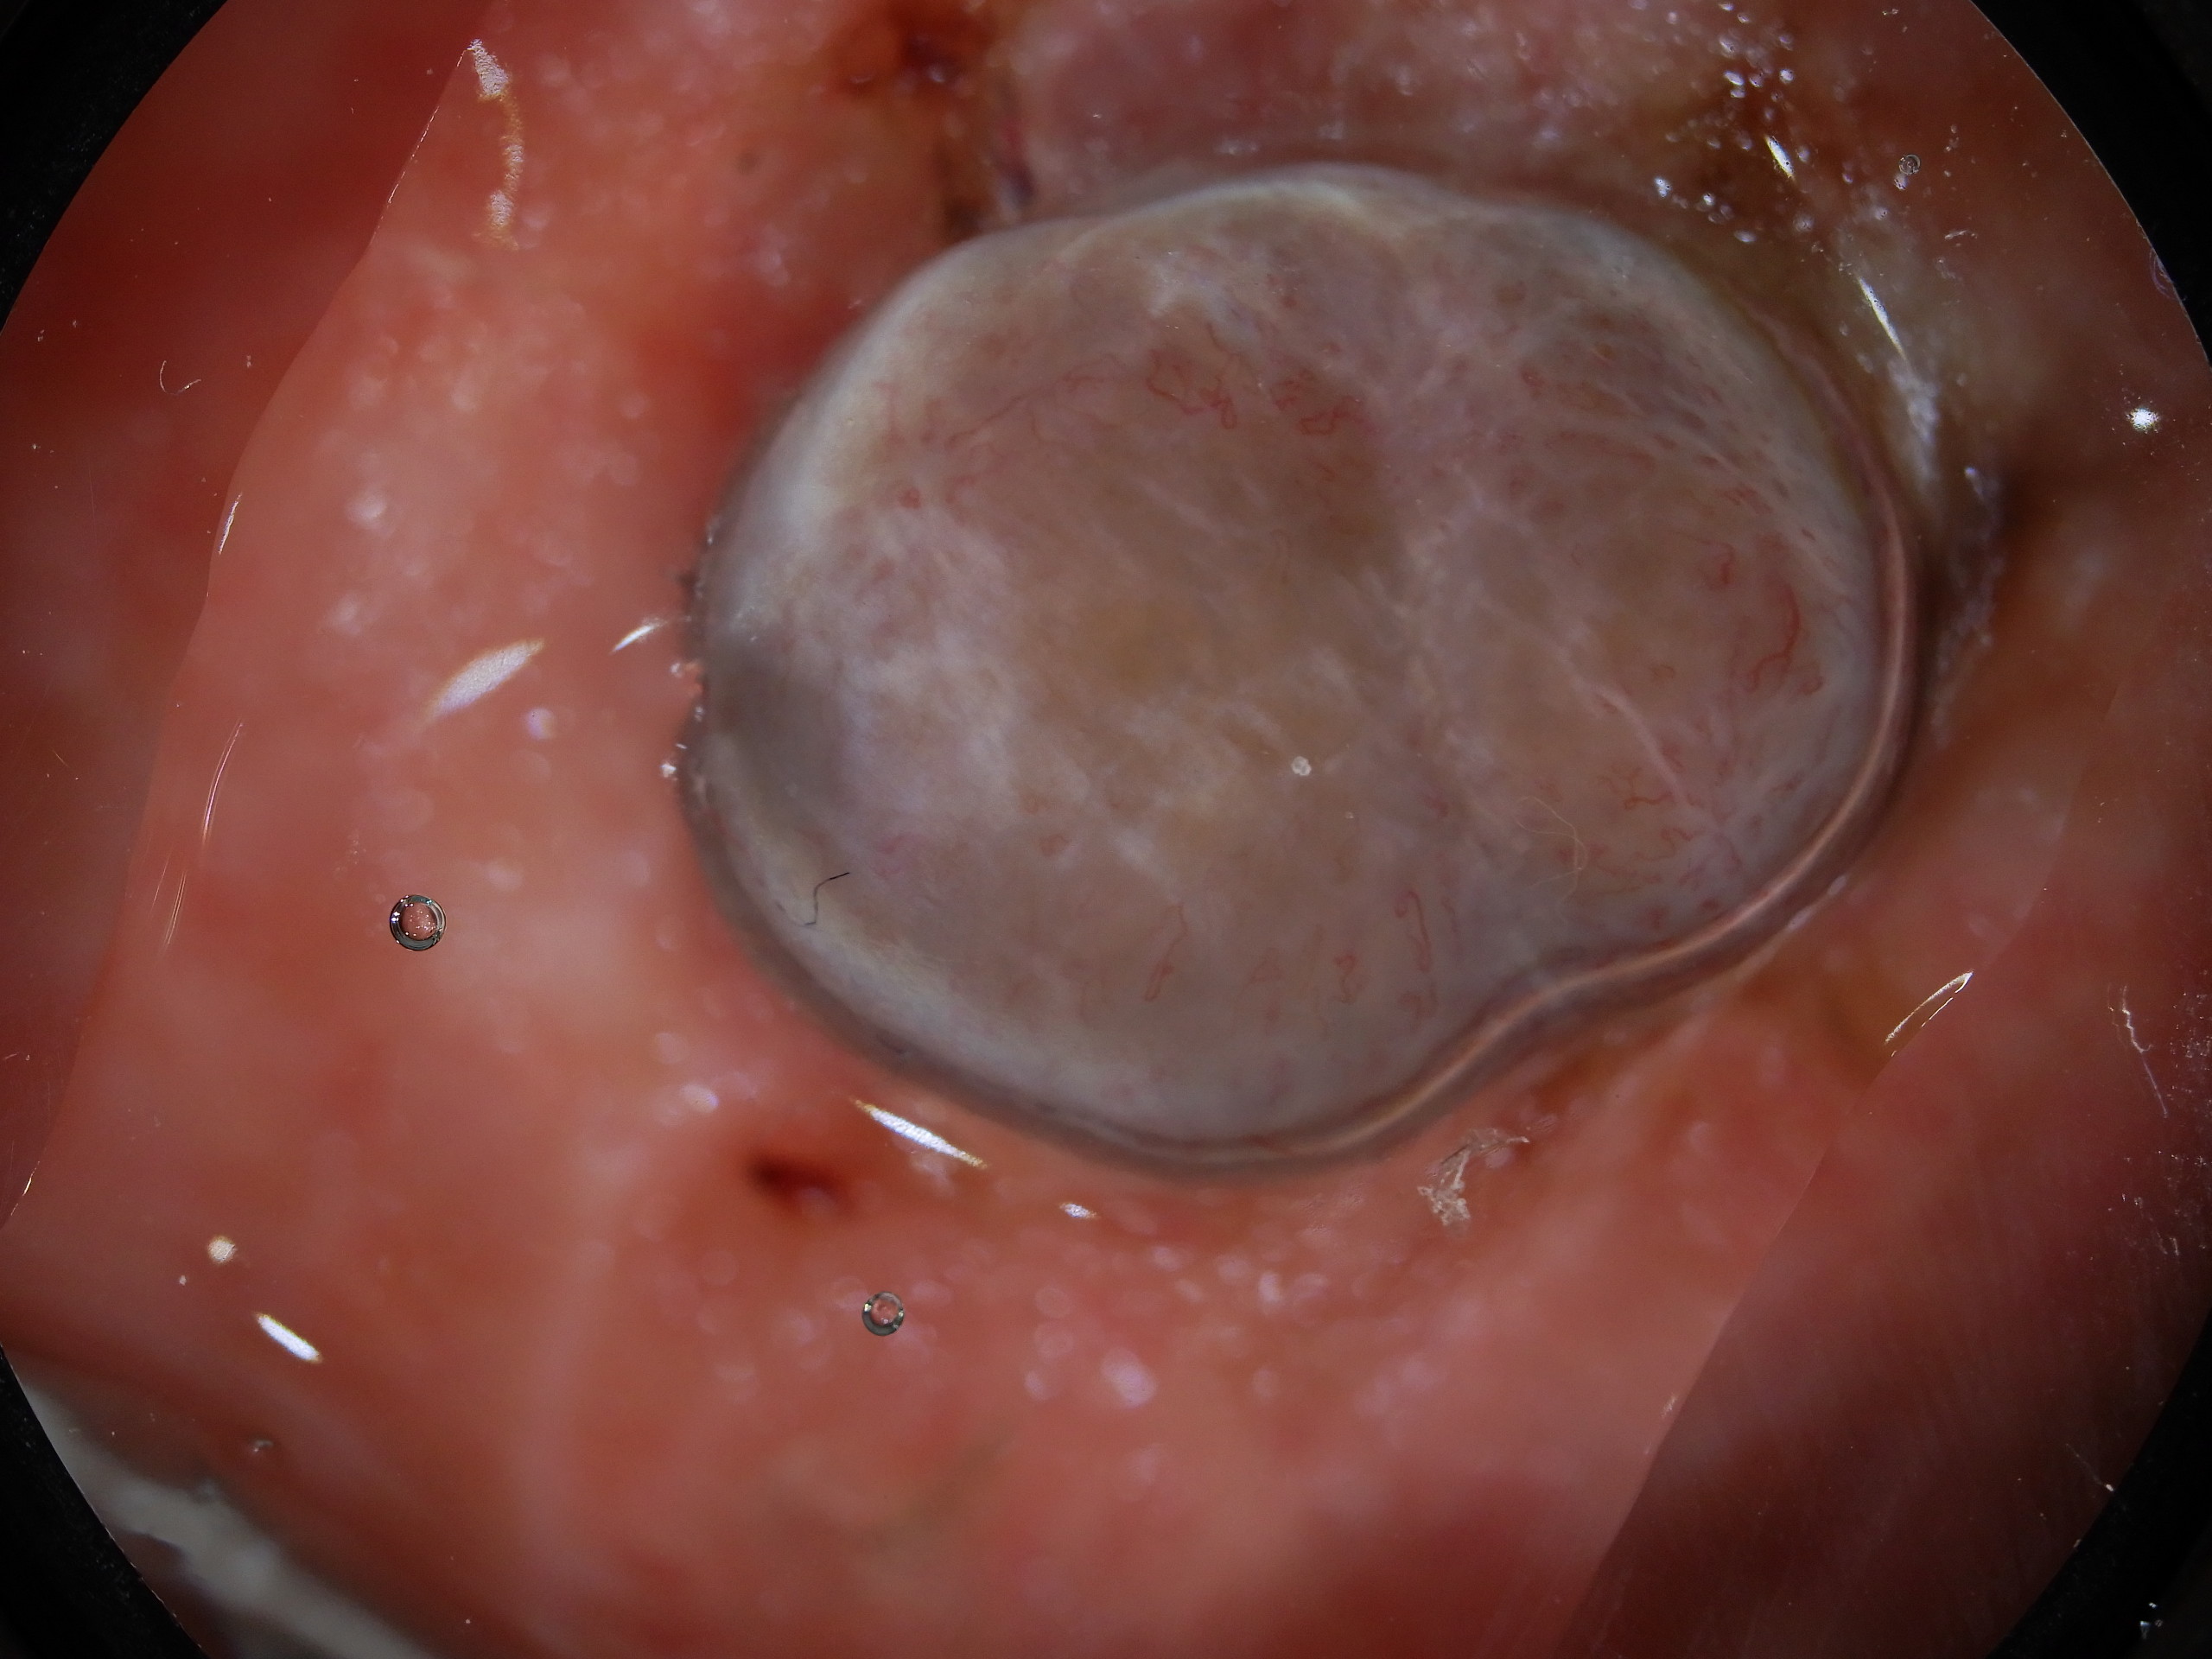

Site: Shins

Diagnosis: Melanoma nodular

Type: Dermlite Polarised

Submitted By: Ian McColl

Description: Blue grey nodule on the shin

Past history of several melanomas including a blue nevus like melanoma metastasis. Rapid growth over 6 weeks of this blue grey nodule on the shin. No local glands in groin. This was a 6 mm thick pigmented nodular melanoma. Compare it with the previous case.